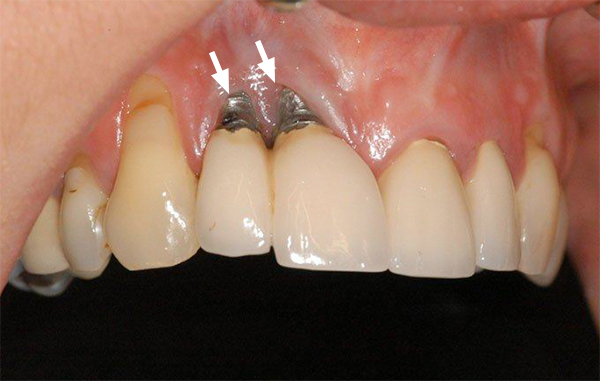

- Trụ Implant đặt sai vị trí hoặc thực hiện sai kỹ thuật: Việc trụ bị nghiêng, đặt lệch hoặc quá sát dây thần kinh có thể tạo áp lực lên vùng xương hàm, gây ra cảm giác đau nhức dữ dội.

- Điều chỉnh hoặc thay đổi trụ Implant nếu cần thiết: Nếu phát hiện trụ đặt sai vị trí hoặc lỏng lẻo, bác sĩ có thể tháo bỏ trụ cũ và cắm lại vào vị trí chính xác hơn.